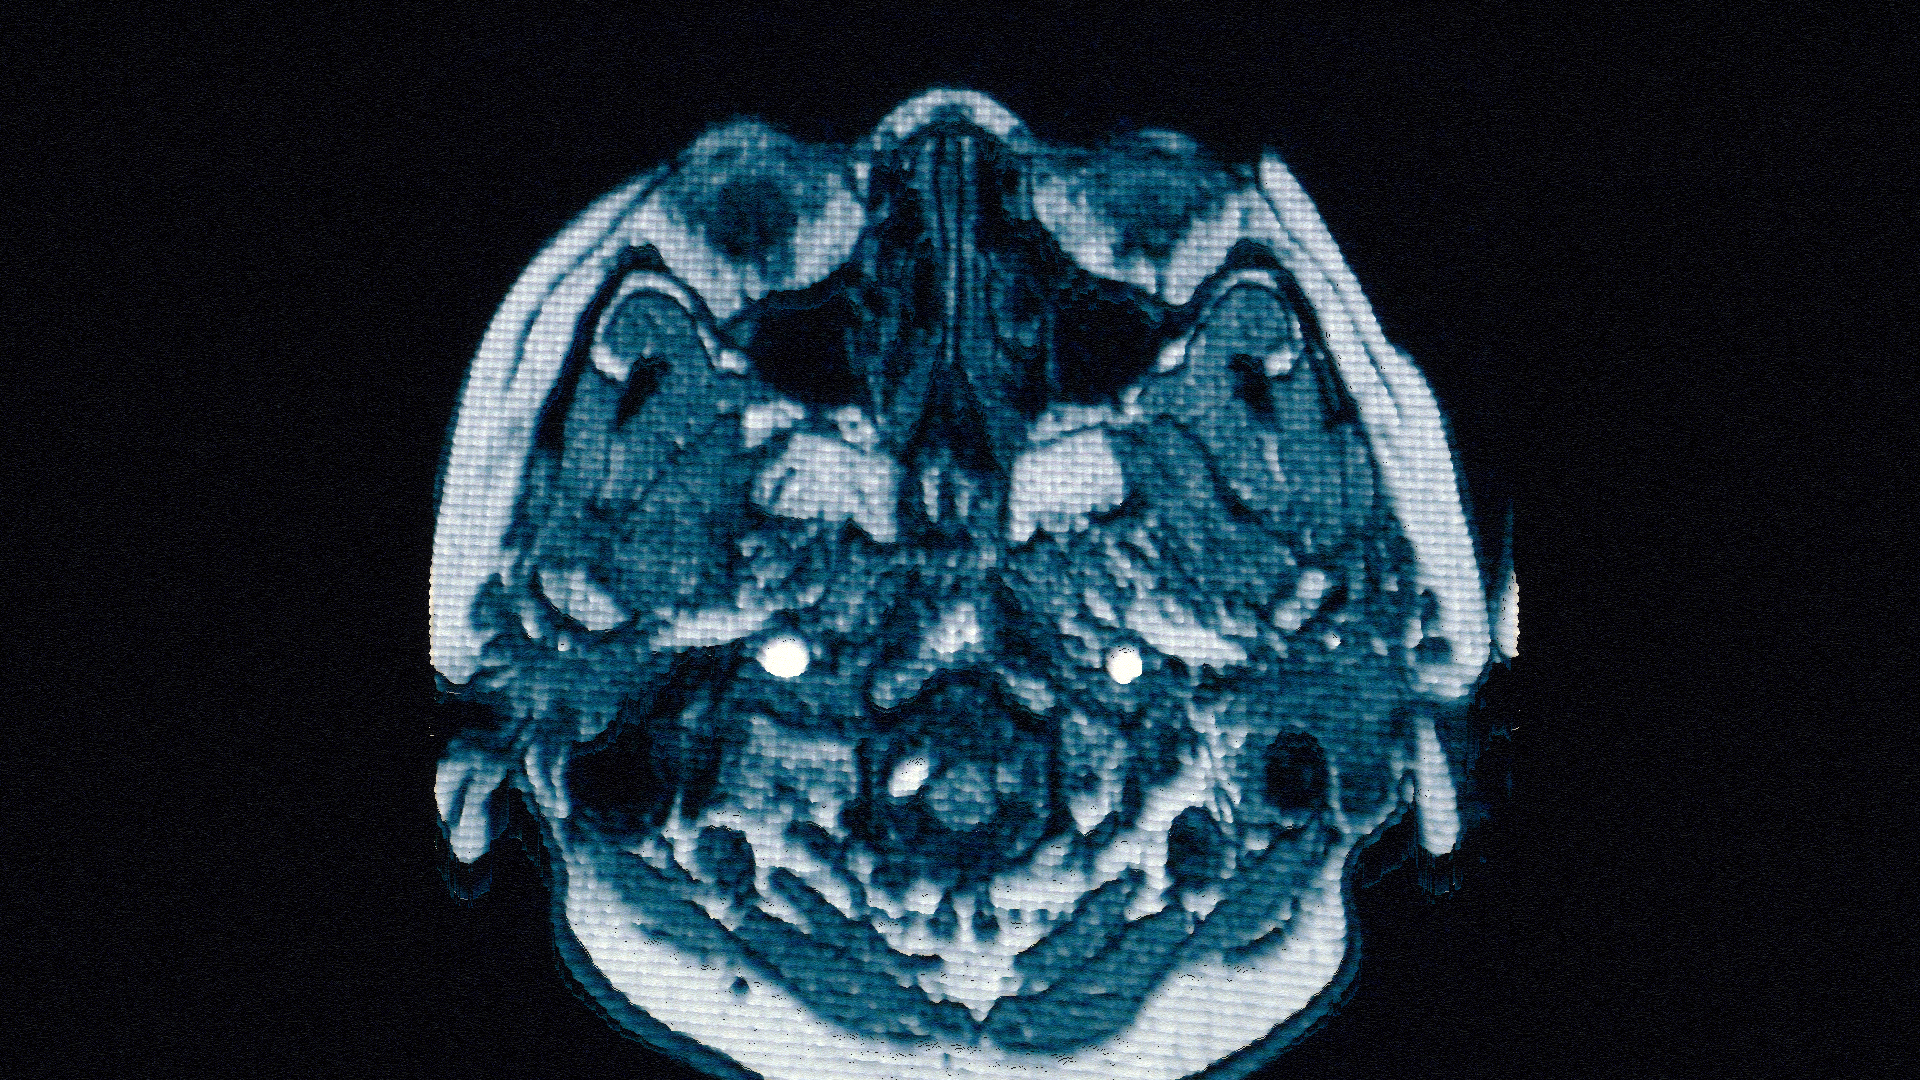

I recently developed style frames and animations for a television commercial. The main topic of the ad was to reflect Alzheimer's disease and what happened in the patient's brain.